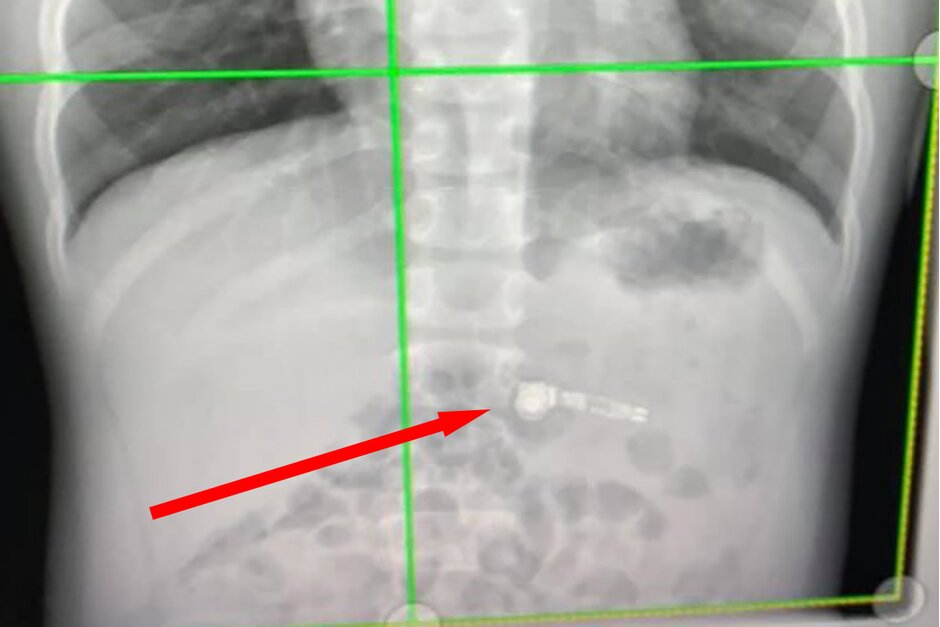

03/01/2020 17:31Nuốt AirPods, bé trai 7 tuổi nhập viện

Hôm qua 2/1, trang PhoneArena đưa tin, cậu bé Georgia 7 tuổi đã buộc phải nhập viện vì nuốt một bên tai nghe AirPods vào bụng. Đây là món quà mẹ cậu bé tặng nhân dịp Giáng sinh.

Tại bệnh viện chăm sóc sức khỏe trẻ em Atlanta Egelston, sau khi chụp x-quang ổ bụng, các bác sĩ đã xác định được vị trí của chiếc AirPods.

Cũng theo PhoneArena, đứa trẻ tỏ ra rất lo lắng. Các bác sĩ nói rằng chiếc tai nghe sẽ thoát ra ngoài theo đường bài tiết tự nhiên.